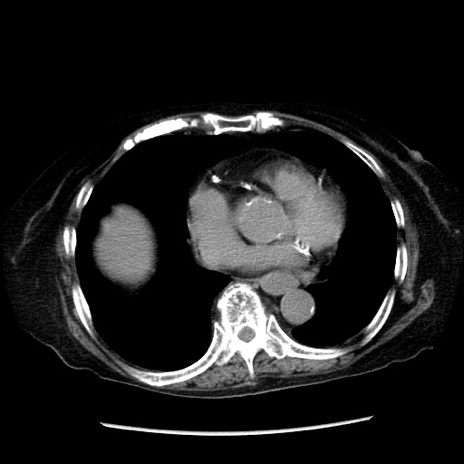

冠状断像

【症例】 90歳代女性

【主訴】 腹痛・嘔吐

【現病歴】今朝から左側腹部痛を認めた。 経過観察していたが、嘔吐を認めたため来院。

【既往歴】 子宮癌術後

【身体所見】 意識清明、BP 127/54mmHg、P 98bpm Sp02 95%(RA)、BT 35.8°C、腹部平坦・軟腸ぜん動音聴取良好、右下腹部圧痛(+) 反跳痛なし

【データ】WBC 9800、CRP 0.46